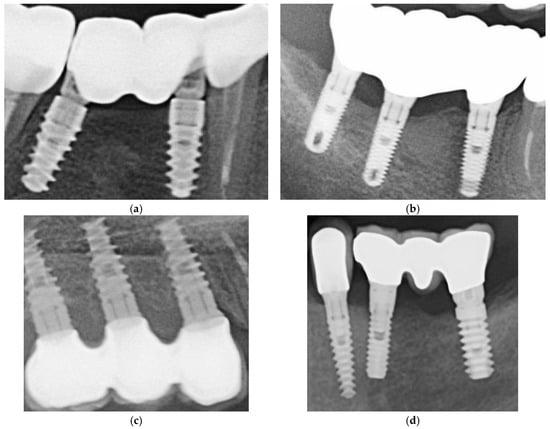

Although these measurements were constrained by image resolution and calibration, they suggested a trend toward smaller marginal discrepancies in restorations cemented with Fuji Plus® compared to those cemented with DentoTemp™. Representative radiographic examples from the study are presented in Figure 8.

Figure 8.

Sections of OPGs from study cases. The left panels (a,c,e,g) show restorations cemented with Fuji Plus®, while the right panels (b,d,f,h) show restorations cemented with DentoTemp™. Images illustrate representative follow-up cases used for radiographic evaluation of retention and marginal adaptation.